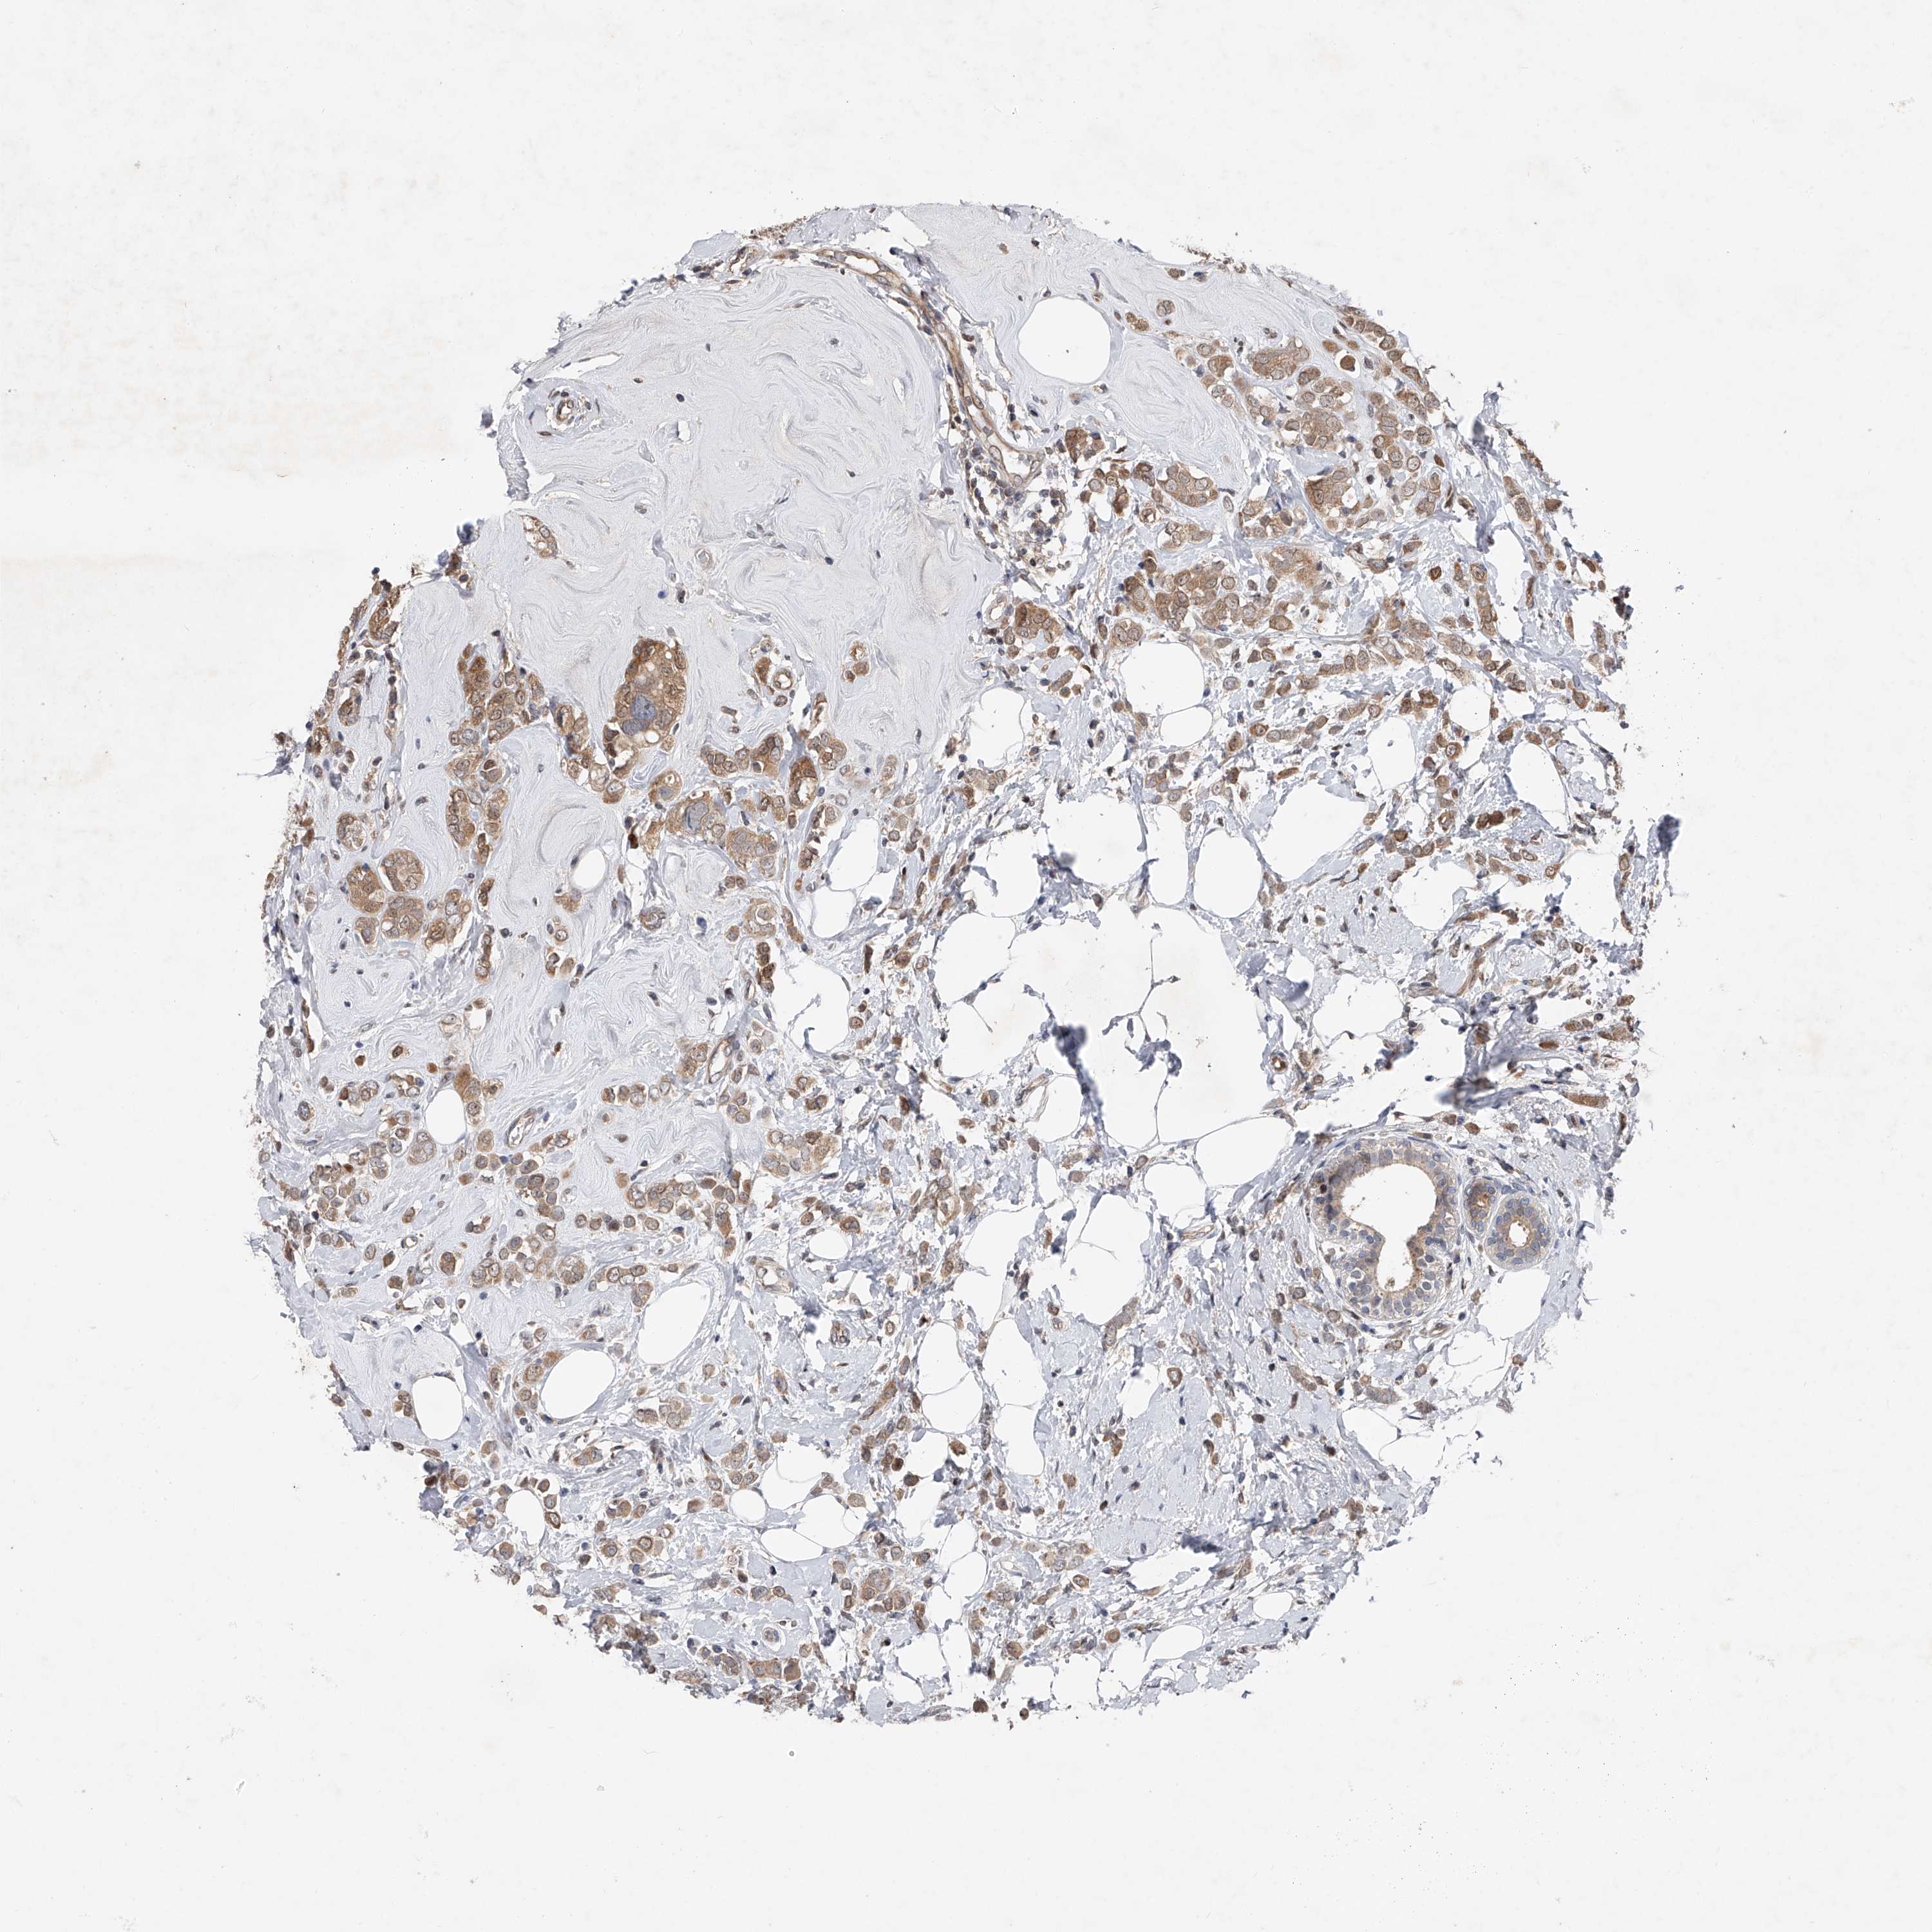

CANCER BREAST CANCER Show tissue menu

BRCA TCGA BRCA VALIDATION PROTEIN EXPRESSION